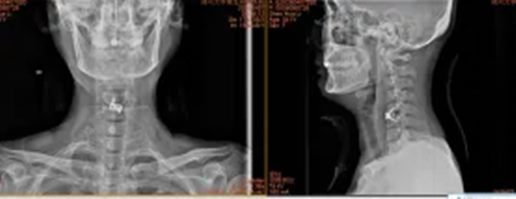

4.郑州市新密市米村镇赵女士60岁

640 (4)_副本

640 (5)_副本